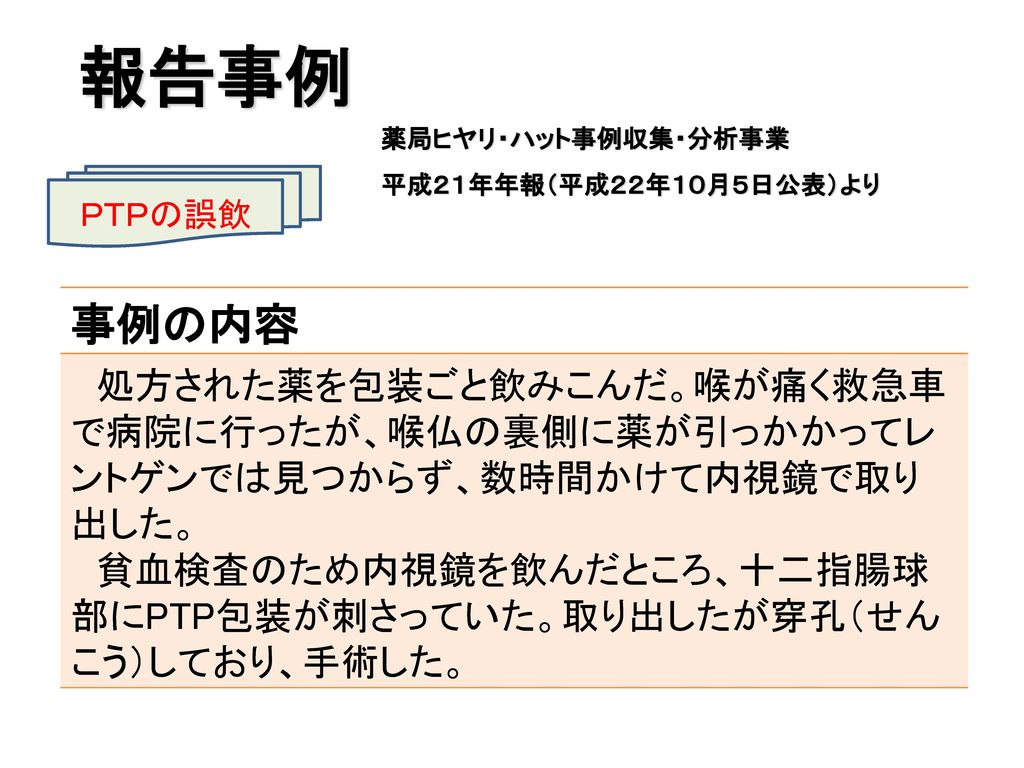

ptp包装シートの誤飲 平成23年4月 日本薬剤師会 Ppt Download

ptp包装シートの誤飲 平成23年4月 日本薬剤師会 Ppt Download

ptp包装シートの誤飲 平成23年4月 日本薬剤師会 Ppt Download

Ppt ptp包装シートの誤飲 Powerpoint Presentation Free